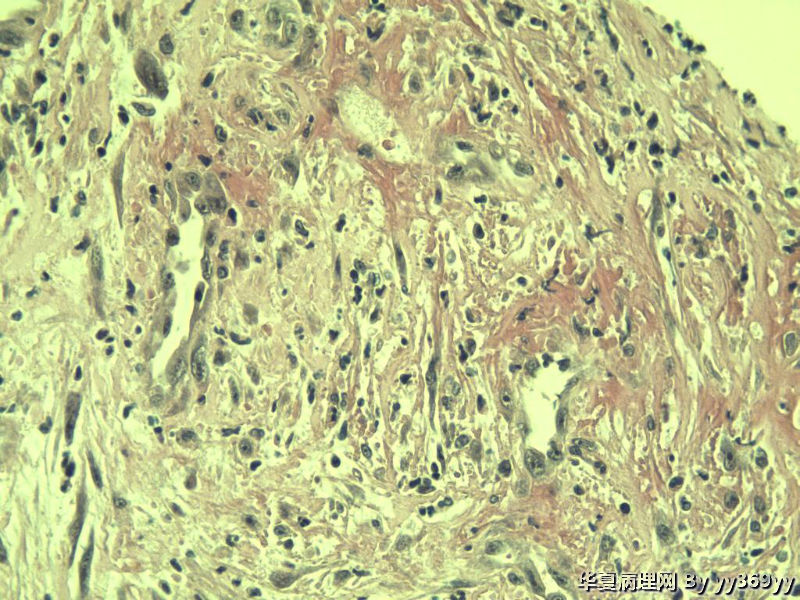

恶性的血管瘤??

男 30岁 小肠一段,肠管严重粘连可见一体积为 2.5 × 2 × 1.5 cm3的肿块,切面灰白,实性,质中

恶性的血管瘤??图4

肿块确切位置?图片颜色不正,需要考虑的有:脂肪坏死/腹腔纤维瘤病/炎性肌纤维母细胞瘤等。

纤维瘤病?

还有GIST需要鉴别